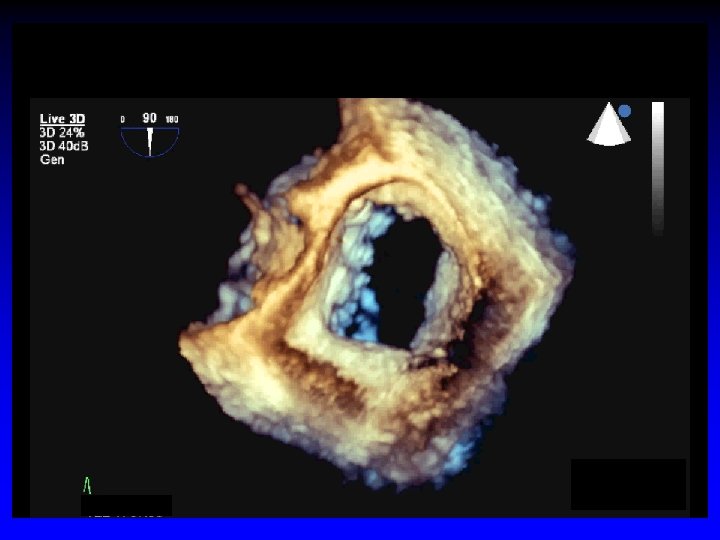

Case 3 Ruptured cords A 2 and A 3

Surgeon’s roadmap A 2 and A 3